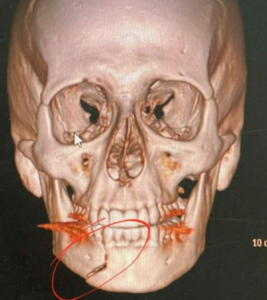

Porém, ele explica que estava em um momento com amigos, quando de repente uma pessoa chegou e o puxou pelo pescoço, em seguida, o agrediu com socos e chutes, que levou a uma fratura exposta na região da mandíbula.